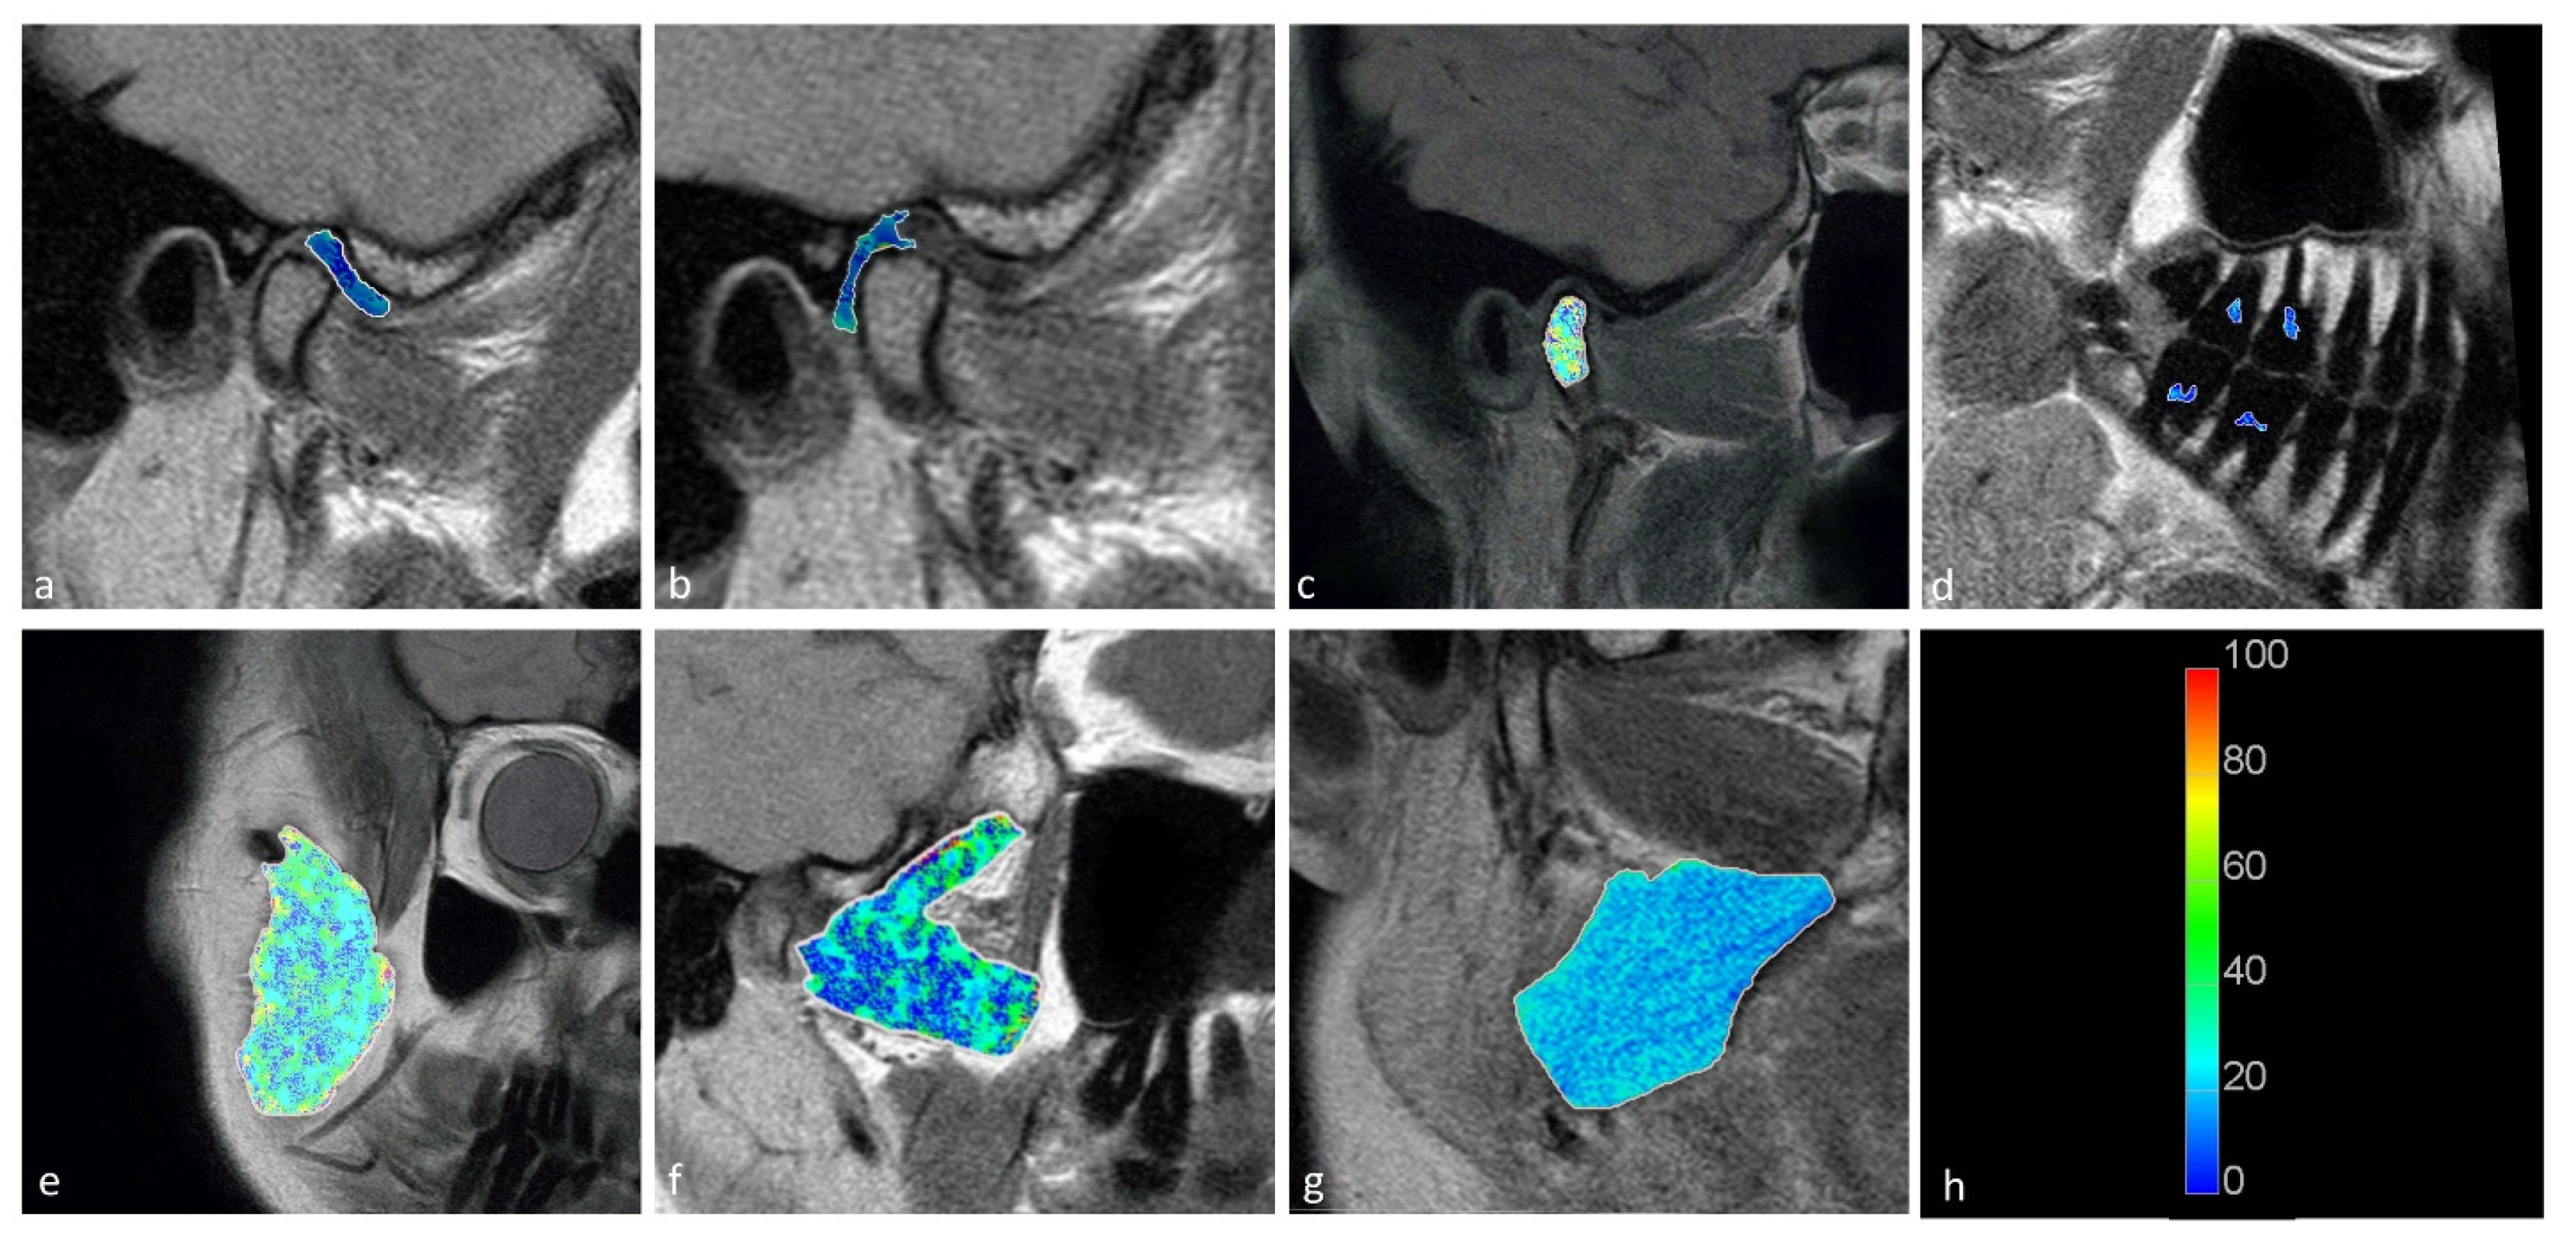

Statistically significant differences were observed between the displaced and nondisplaced disk groups in the retrodiscal tissue short T2 component (p < 0.0001) short fraction (p = 0.0050) and long fraction (p = 0.0049), the medial pterygoid muscle short T2 component (p = 0.0025) as well as the bone marrow long T2 component (p = 0.0030) and short T2 component (p = 0.0116), indicating the relationship between disk displacement and quantitative MRI features of stomatognathic anatomical structures. The pulp short T2 component showed a trend toward statistical significance (0.0125 < p < 0.0500). Sample T2 maps are presented in Figure 2 and Figure 3. Short and long fraction components are presented in Figure 4 and Figure 5, respectively. The Shapiro–Wilk test confirmed normality in all comparisons.

Figure 3. Long T2 maps obtained for the (a) disk; (b) retrodiscal tissue; (c) bone marrow of the condyloid process; (d) pulp; (e) m. masseter; (f) m. pterygoideus lateralis; and (g) m. pterygoideus medialis. (h) Color scale showing the reference T2 times in seconds.